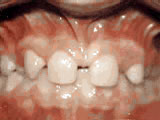

Spacing of teeth

spacing of teeth beforeBefore

spacing of teeth afterAfter

Patient was bothered by the spaces between his teeth. Braces closed the spaces and gave him an ideal bite in 24 months. Special glued-in retainers help keep the spaces closed.